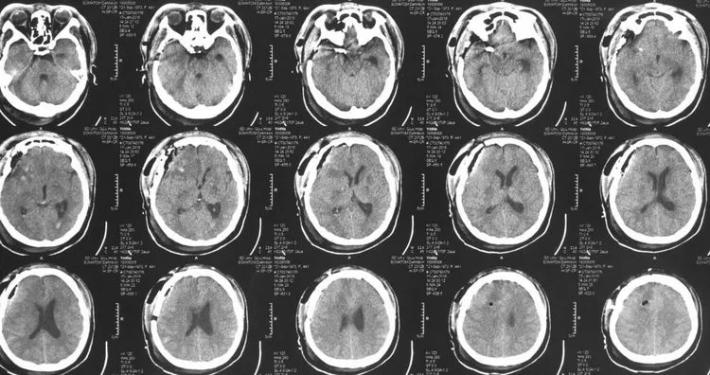

病史简介 患者中年女性,3天前突发头痛伴恶心、呕吐入院。无阳性病史。Hunt一Hess分级I级。CT示SAH,右鞍上池、侧裂根部出血较多。